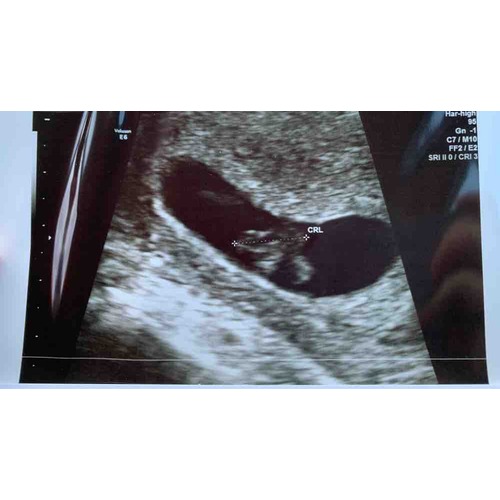

Hoi allen, hoe is het uiteindelijk bij jullie allemaal verlopen? Wij hadden gister onze eerste echo (ongeveer 6.3 wk) en onze Vk was ook wat voorzichtig met goed nieuws brengen door de vorm van de vruchtzak. Echter wel een hartslag; langzaam maar dit hoeft nog niets te betekenen met dit termijn.

Ik heb tijdens bloedverlies twee echo's gehad met een kloppend hartje. Veel stolsels ook om de vruchtzak heen in mijn baarmoeder.

Vier dagen later op de echo geen kloppend hartje meer en de vk zei toen nog dat de vruchtzak er ook niet mooi rond meer uit zag. Dus bij mij was dat helaas geen goed teken.